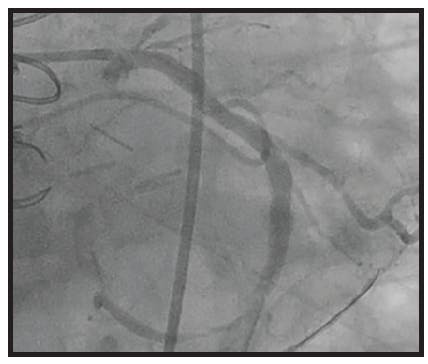

A 92-year-old man with a history of coronary artery disease (treated previously with coronary artery bypass graft) and severe aortic stenosis (treated previously with transcatheter aortic valve replacement) presented to the ED with chest pain. The patient had reported intermittent chest discomfort for 3 days, with some improvement with his daily medications. The pain became more intense and constant, so he presented to the ED. The patient was brought to the catheterization laboratory for angiography that showed stagnant flow through the saphenous vein graft (SVG; Figure 1).

INTERVENTION

We decided to start with mechanical aspiration using CAT RX and Penumbra ENGINE to extract the thrombus. After just one pass with CAT RX and 20 seconds of aspiration, the thrombus was removed. Angiography was performed and confirmed complete thrombus removal and flow restoration through the SVG. We directly stented with a 3.5- X 38-mm Synergy DES and postdilated with a 4- X 20-mm noncompliant balloon. The final angiographic outcome revealed complete revascularization and TIMI 3 flow (Figure 2).